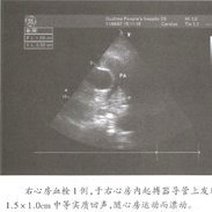

- 超声心动图正常心脏声像图先天性心脏病超声诊断心脏瓣膜病超声诊断心肌病超声诊断冠心病、心脏肿瘤、心包疾病超声诊断内容概述先天性心脏病心脏瓣膜病心肌病冠状动脉粥样硬化性心脏病心脏肿瘤和血栓心包疾病禁忌症适应症概述探头频率成人儿童检查前准备无需特